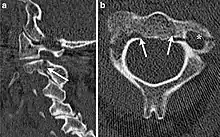

| CT scan of hangman's fracture | |